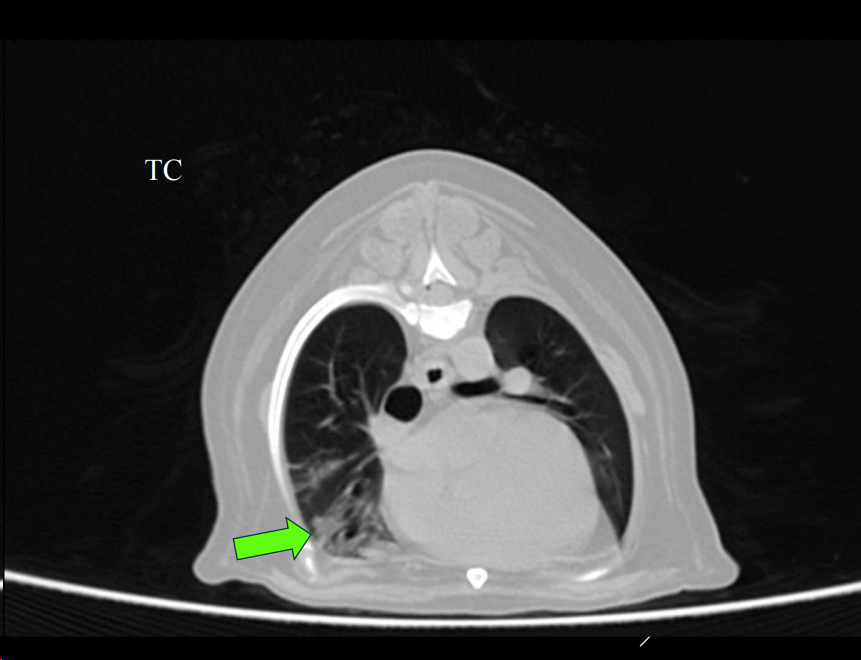

APLICACIONES DEL TC

- Siempre empezamos por una radiografia, ya luego tomogrofia o TC (Al ser mas caro y siendo generalmenta la mayoria de problemas diagnosticables con radiografia)

- Exploraciones radiográficas inconcluyentes.

- Ampliar información de estudios radiográficos.

- Diferenciar entre lesión mediastínica, pulmonar, pleural o pared torácica.

- Detectar metástasis de pequeño tamaño o tromboembolismos pulmonares.

- Evaluar la lesión previo a cirugía.

- Toma de biopsias guiada.